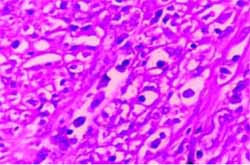

Los múltiples cortes de la masa mostraron un tejido fibroso con histiocitos, plasmocitos, neutrófilos escasos y eosinófilos sin evidencia de neoplasia maligna ni de procesos granulomatosos tuberculosos a ningún nivel. (Figura No 2). La inmunoperoxidasa mostró actina muscular positiva, CD20 negativa en fibroblastos y CD68 positiva en infiltrados linfoides.

Figura No. 2